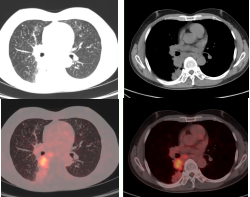

肺癌放疗前确定生物靶区:左肺下叶鳞癌患者(右图所示),左下肺癌病灶并远端阻塞性肺不张,PET/CT可以准确区分肿瘤组织与非肿瘤组织,确定肿瘤病灶生物靶区。

早期肺癌发现及鉴别:PET/CT显像示左肺上叶前段软组织灶(左图所示),糖代谢明显增高(SUVmax=15.3),经手术病理证实为肺腺癌。